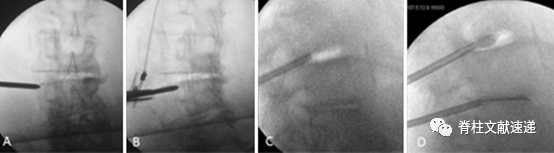

患者全麻后俯卧于手术台上,胸廓和骨盆下方放置两个气垫,以减轻腹部的压力。双膝关节下方放置气垫以增加脊柱前凸,从而使椎间隙充分打开。

图注:A:患者术中体位;B:在C臂透视下经皮穿刺置入穿刺针;C:术中可使用肌电监护以防止神经受损;D:缓慢注入骨水泥